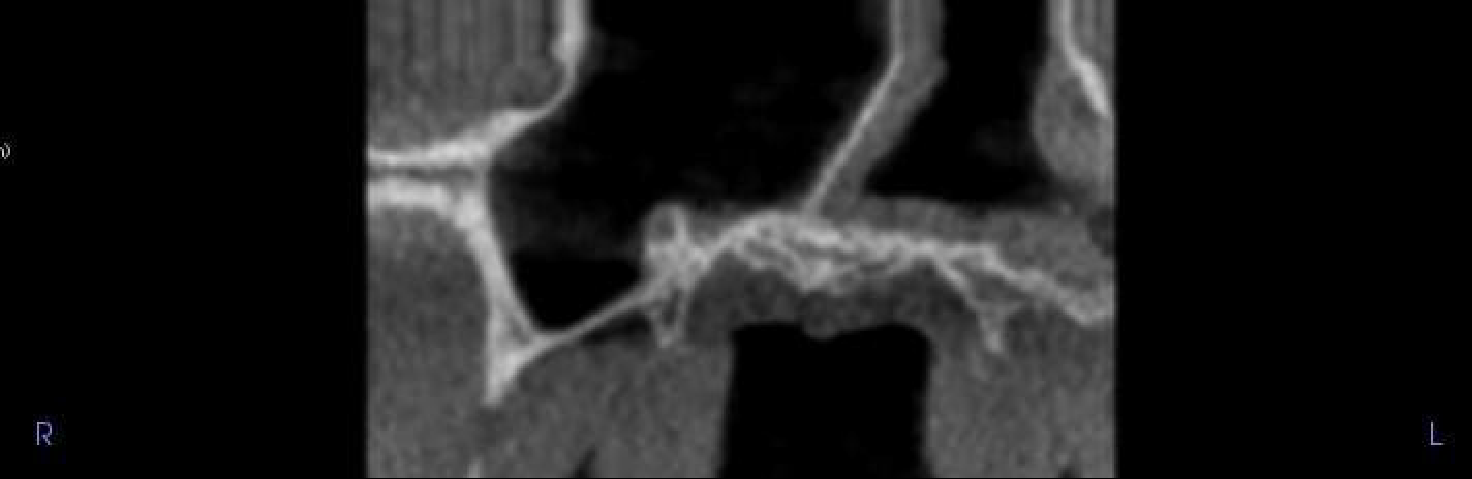

UL7 edentulous ridge. Well defined radiopacity extending from the alveolar bone crest to the sinus floor